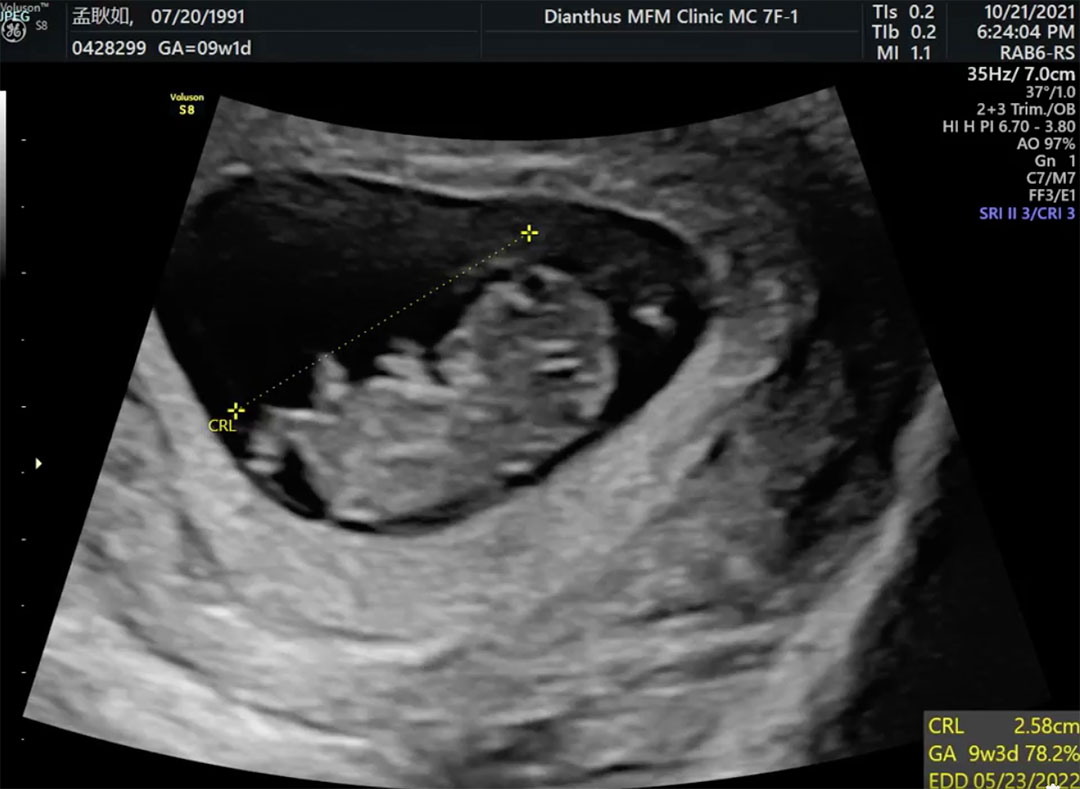

孟耿如與黃子佼愛情長跑7年,於2020年登記完婚。有19歲年齡差距的兩人長久以來一直在「要生小孩/不生小孩」中糾結,但最終還是達到共識。孟耿如近日開心宣布自己已懷孕3個月,並分享寶寶2個月照超音波的影片!

雖然胎兒才兩個月,但已經可以看出大大的頭、短短的四肢看起來真的超可愛,而且寶寶看起來真的很活潑喔~小手手揮個不停!小小年紀就知道要對鏡頭打招呼,看來也是個喜歡表演的孩子XDD(妞編輯姨母笑)